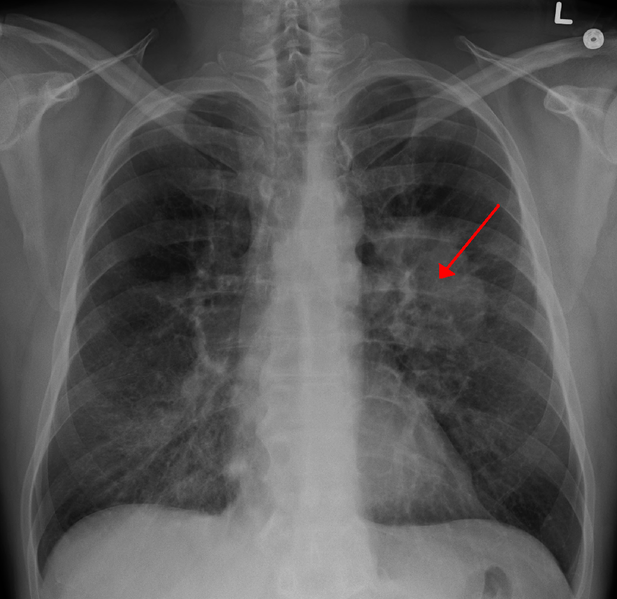

A new lung cancer treatment has seen some success Photo Courtesy of Dr. James Heilman

New treatment decreases deaths from lung cancer

Elinor Higgins | April 18, 2018

Most of us know from our high school health classes that we should avoid smoking because it can cause lung cancer. Many students were presented with disturbing visuals that compare healthy lungs with a...